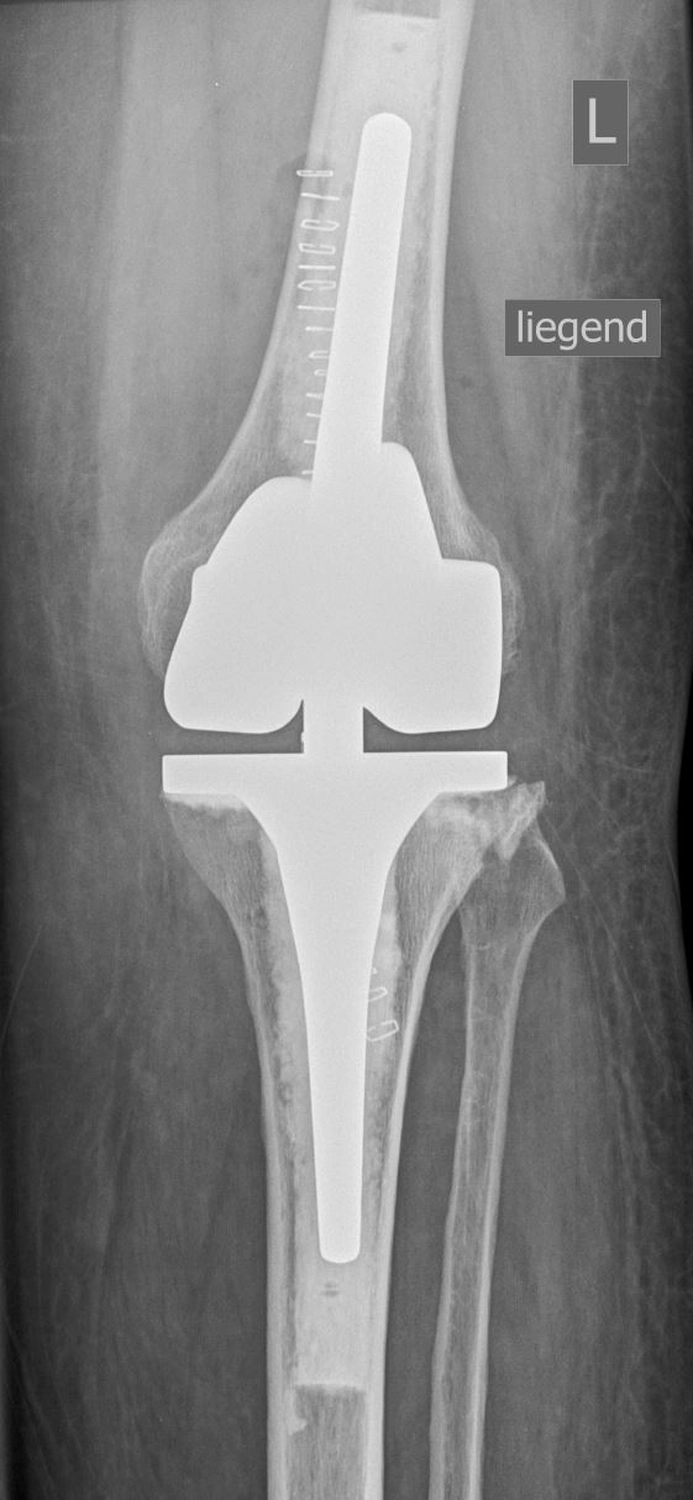

Bei der Implantation einer Knieprothese werden die zerstörten Gelenkflächen des Oberschenkel- und Schienbeinknochens millimetergenau entfernt und durch passgenaue Metallkomponenten ersetzt.

Dazwischen liegt ein hochbelastbares Kunststoffinlay, das die Gleitfläche bildet.

Bei der Implantation einer Knieprothese werden die zerstörten Gelenkflächen des Oberschenkel- und Schienbeinknochens millimetergenau entfernt und durch passgenaue Metallkomponenten ersetzt. Dazwischen liegt ein hochbelastbares Kunststoffinlay, dass die Gleitfläche bildet.

Je nach Schädigung und Gelenkzustand werden unterschiedliche Prothesenarten verwendet:

Die Operation dauert etwa 60 bis 90 Minuten und erfolgt unter Voll- oder Spinalanästhesie.